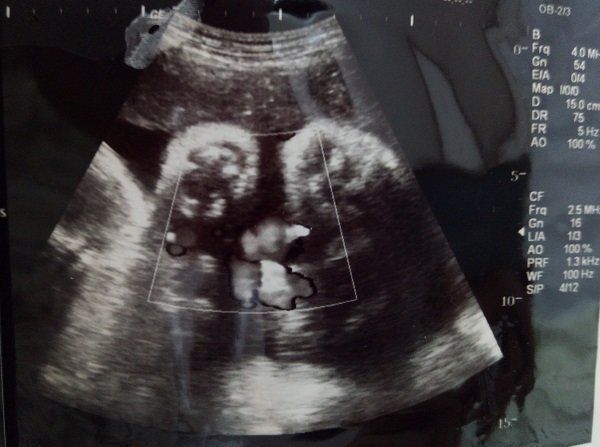

妊娠26週のエコー写真 4Dエコーに感動

初めて4Dのエコーで検査をしました。この日に性別を教えてもらえることになっていたので、とても楽しみに臨んだ検査では、股をしっかり開いて「男の子」を主張してくれました。右側に映るのが赤ちゃんの横顔です。顔がはっきりと見え、嬉しくて何度も見返していました。でも鼻が低いのが私に似ているようで、「可哀そうに」とも思っていました。